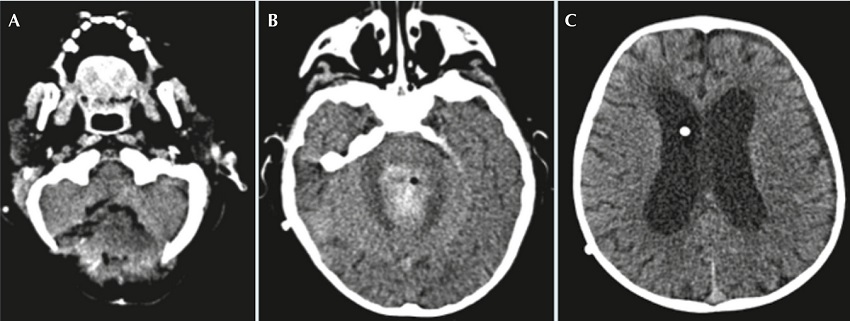

Al décimo día de la craniectomía presentó endotropía, somnolencia e hipertensión, realizándose tomografía axial computarizada cerebral donde se encontró hematoma hiperdenso residual en el lecho quirúrgico y se observó nuevo incremento en la talla ventricular, por lo que pasó a quirófano para exteriorización del sistema de derivación ventrículo peritoneal por hemorragia intraventricular (Figura 4). Se agregó fiebre hasta 38.6ºC de difícil control, por lo que se inició esquema antibiótico con ceftriaxona y vancomicina a dosis de sistema nervioso central, para cobertura de bacilos Gram negativos y cocos Gram positivos, respectivamente. En el cultivo de líquido cefalorraquídeo hubo desarrollo de Pseudomonas aeruginosa por lo que se suspendió ceftriaxona y se inició meropenem (120 mg/kg/d). Se reportó antibiograma de P. aeruginosa con resistencia a carbapenémicos, sensibilidad intermedia a piperacilina/tazobactam y sensibilidad a cefalosporinas de cuarta generación, por lo que se suspendió meropenem y se inició cefepima (150 mg/kg/d).

El paciente presentó deterioro clínico, somnolencia y dificultad respiratoria por lo que se pasó a ventilación mecánica y se realizó otra tomografía axial computarizada que mostró abundante líquido con detritus sugestivos de pus. Por este motivo, se decidió re-intervenir quirúrgicamente para retirar el sistema de derivación ventrículo peritoneal y colocar ventriculostomía externa (Figura 5). Posteriormente, continuó hemodinámicamente inestable, con datos clínicos de choque séptico sin respuesta a manejo intensivo persistiendo con taquicardia, hipertensión arterial y disminución en la saturación de oxígeno; finalmente, presentó paro cardiaco sin respuesta a maniobras de reanimación.